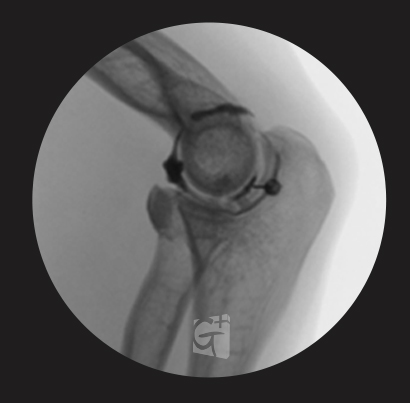

팔꿈치 치료

테니스 엘보 / 골프 엘보 등

염증부위에 주사 시술 -